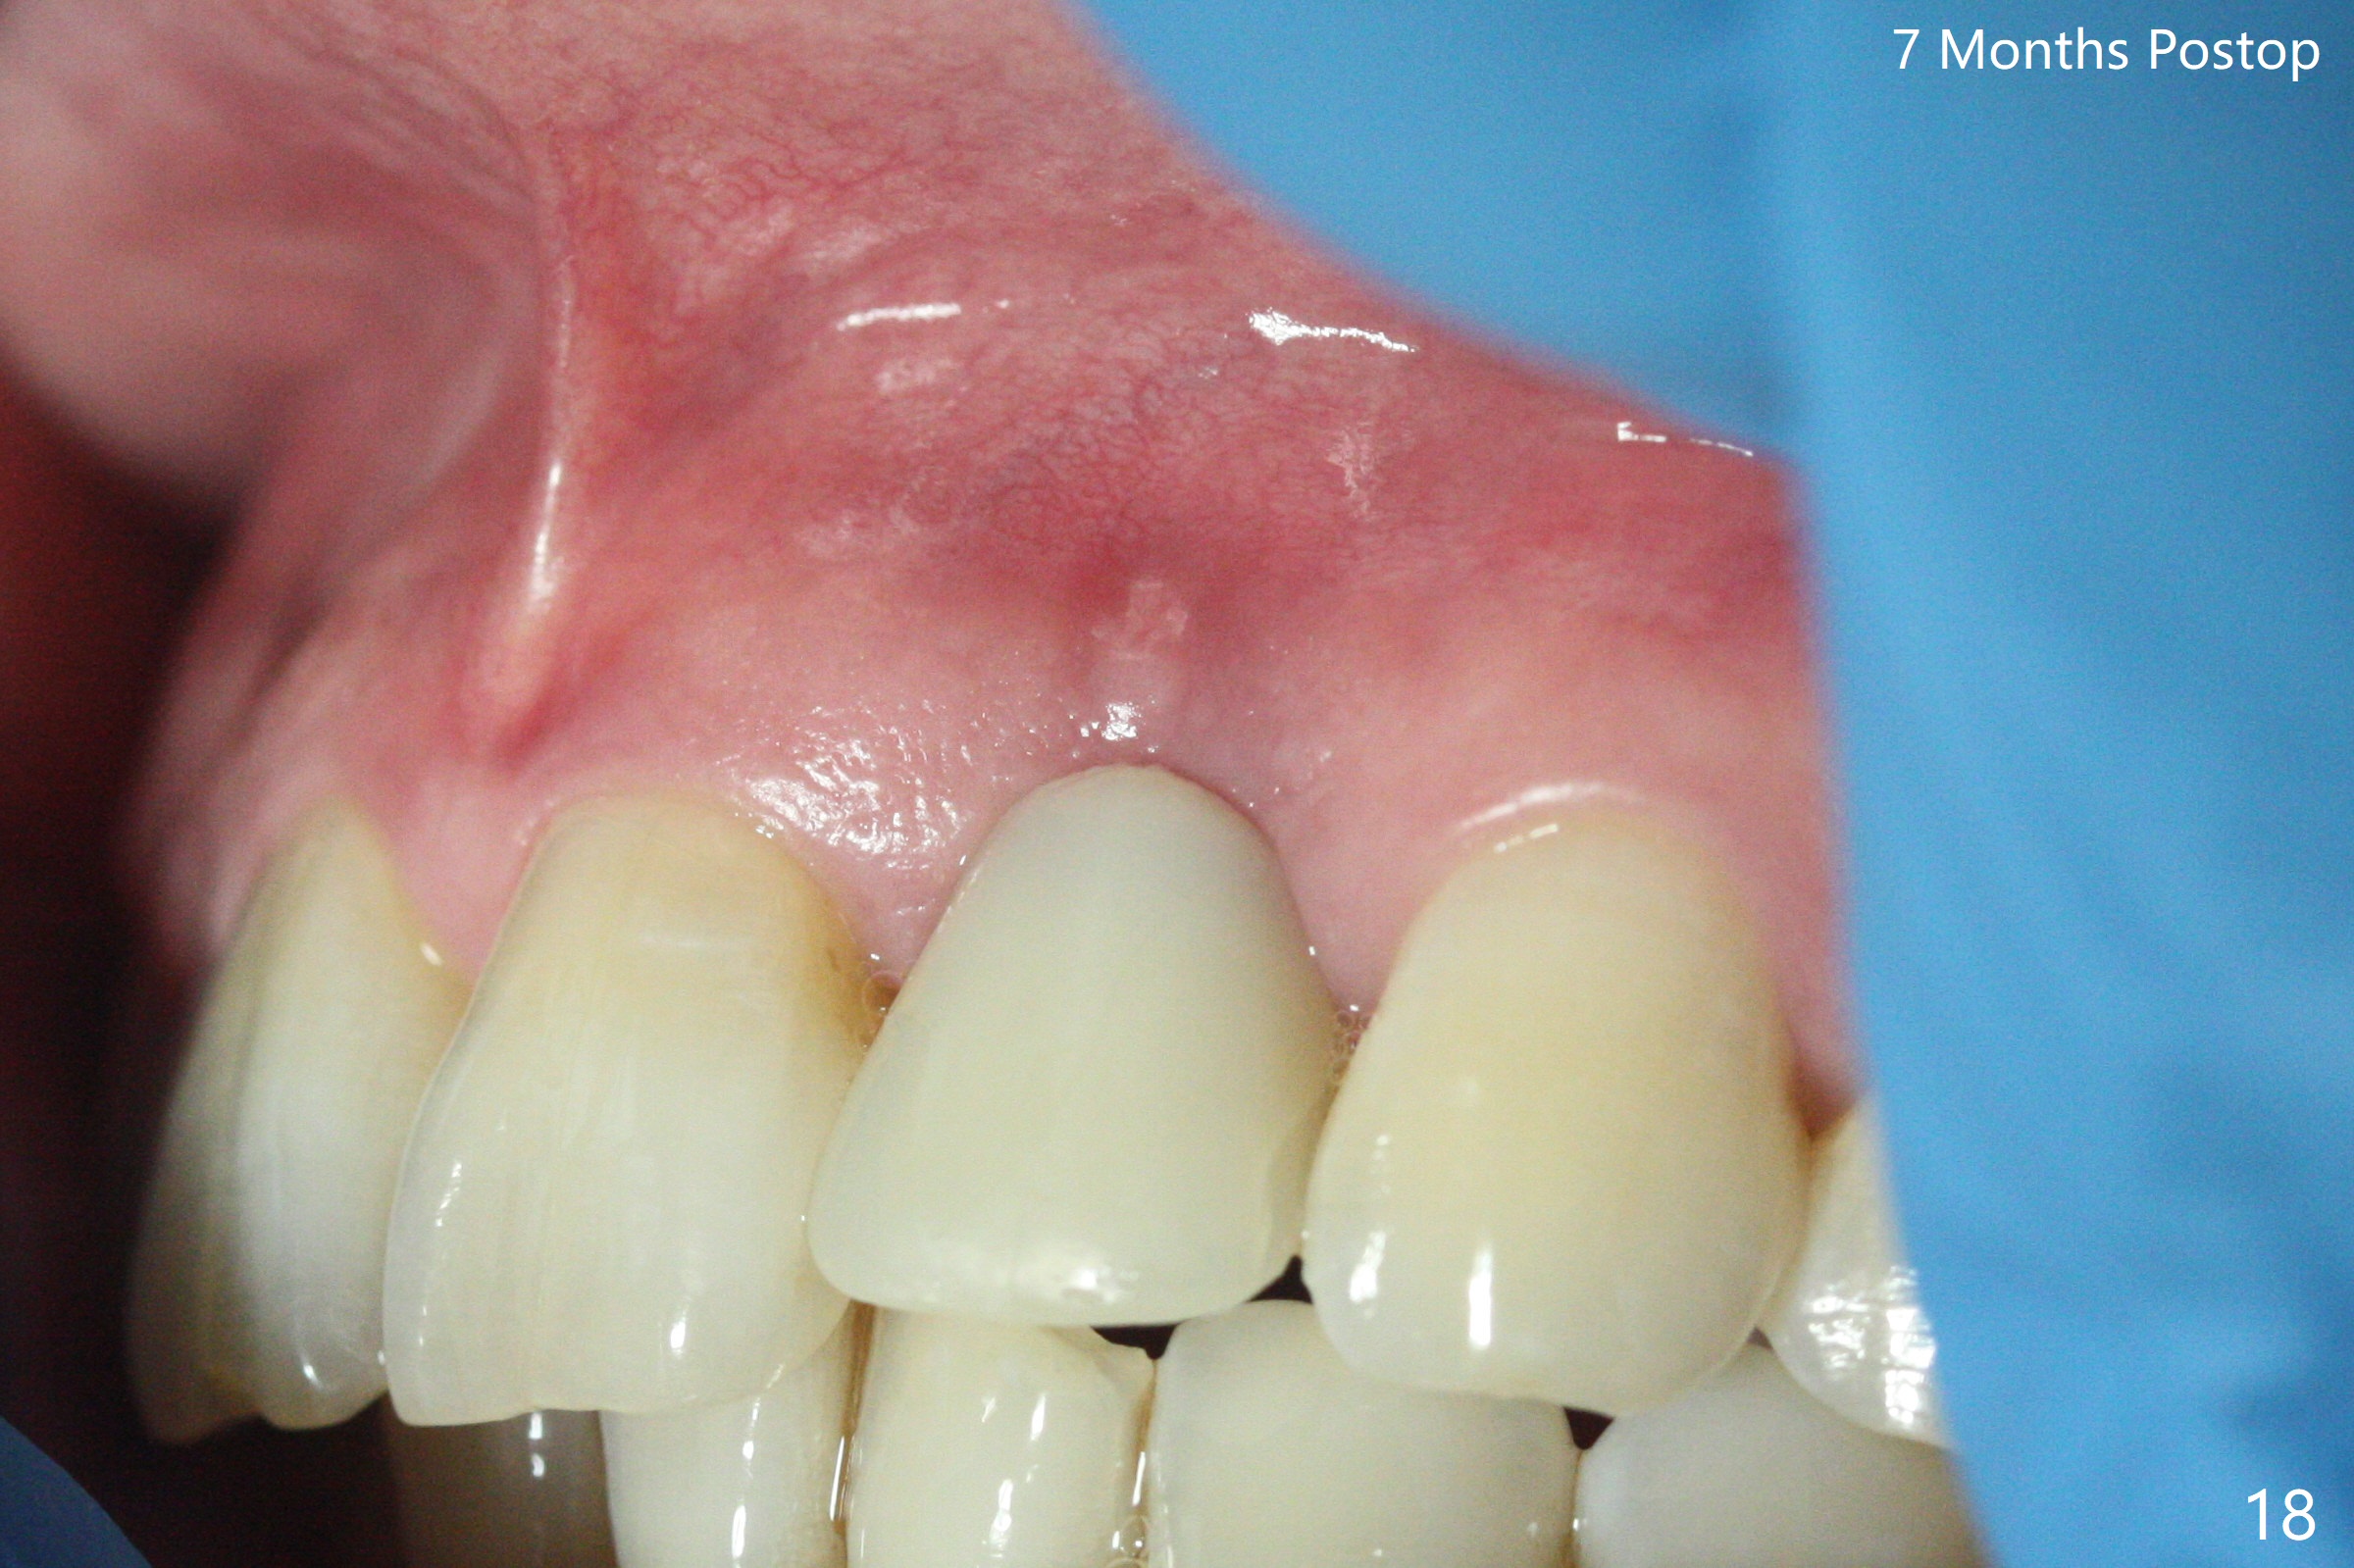

病人回来带来瘘道(图一),不过不会增加难度,病牙去除,它便自动消失。尽管颊侧骨壁完全失去,颊侧牙龈仍丰满(图二),为什么呢?第一,因为粗大牙根存在,第二两旁牙齿,牙槽骨撑着帐篷(侧切牙颊侧牙龈),第三,牙冠。为了防止术后牙龈塌陷,尽量不切开,即刻放置植体(牙根);由于前牙缘故,这次植体不能很大,所以植骨必须过度(over grafting),最后即刻制作临时牙冠,撑住牙龈。这就是所谓每个人进入角色。这个牙根有一种先天性畸形:dens in dent (图三(腭侧观):箭头)。尽管腭侧牙根畸形,腭侧骨壁吸收临床上并不严重,所以钻洞仍偏腭侧。当预定最后钻头还在钻洞时,填入大量粘性骨块(图四:*),细长植体还没有完全卡入鼻底(图五),最后好像可以(图六,七)。植体,骨粉入位(图八),最后临时牙冠出场(图九)。尽管植体小,术后一周临时牙冠仍然可以维持牙龈原有形状(emergency profile,图十:箭头(*:树脂强化牙冠固定))。图十一以不同角度显示瘘道缩小。术后三周取出有些松动的临时牙冠,骨粉虽然还没有被肉芽组织整合,但是显得正常,周围牙龈健康(图十二)。术后4个月牙龈形态正常(图十三),没有触痛;颊侧骨板轻度凹陷(图十四);骨粉仍在原位(图十五)。术后7个月骨粉仍在原位(图十五,十六,但是冠部密度减低(可能骨粉流失,需要牙周或者树脂敷料保护)),没有螺纹暴露。但是牙冠边缘暴露,说明牙龈收缩(图十七,与图十三对比),颊侧骨板仍塌陷(图十八)。插入龈线取得多个目的:修整基台边缘,取模,颊侧牙龈推向颊侧,有利于即将衬里牙冠龈缘进入龈下(图十九)。取模后牙冠边缘(图二十:<)衬里,然后修整,变窄,以便插入龈下,促进颊侧牙龈下降(图二十一,二十二)。术后8个月牙冠粘固前牙龈健康(图二十七,八),牙冠(图二十九)固位后,病人满意(图三十),咬合调整(图三十一),注意腭侧粘固粉流出通道(<)。